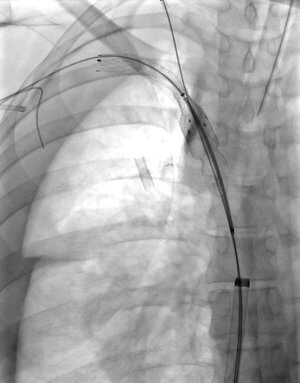

28 year old female patient with CKD requiring dialysis through a right upper extremity AV fistula. She presents with right upper extremity swelling.

Comment: This chronic occlusion was recanalized using the PowerWire RF Guidewire (Baylis Medical). Access was gained from the internal jugular vein as well as the common femoral vein in order to the potential for relatively straight line passage of the PowerWire. Once access was achieved via all of these veins, a snare was positioned in the SVC and the PowerWire was introduced via the right internal jugular vein. Passage of the wire was found to be extravascular in this case, so covered stents were used to cover the area of occlusion in the proximal subclavian vein extending into the brachiocephalic vein and the upper SVC.